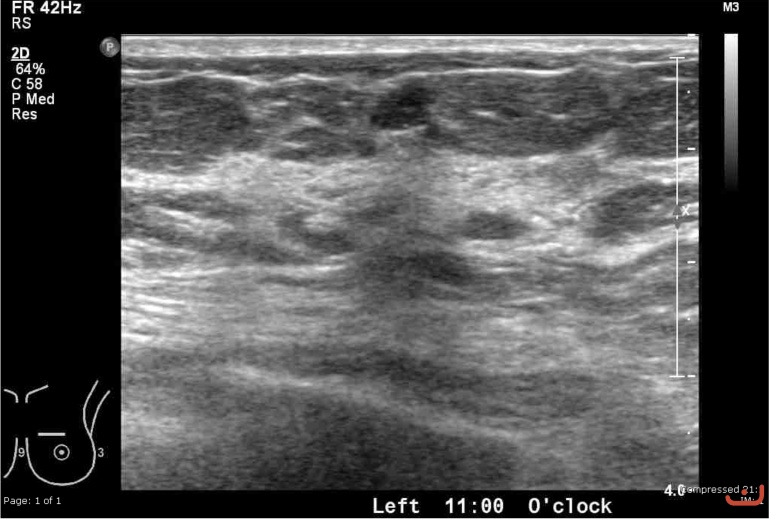

Malignant solid mass

Thursday, 30 April 2015

192.45 KB (769 x 519 px)